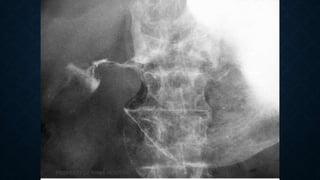

This document provides an overview of x-rays for medical students, covering topics such as ensuring x-rays are well-aligned, exposure levels, common artifacts and anatomical features, abdominal x-ray positions and views, and specialized x-rays including barium swallows, enemas, and tests to examine the esophagus, small bowel, biliary tree, and kidneys.